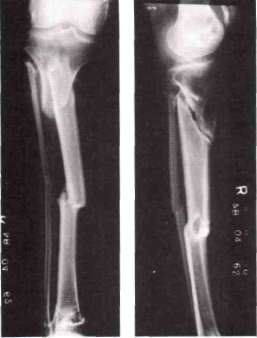

P.S. was born on February 28, 1953. He suffered from congenital pseudarthrosis of the right tibia and fibula, essentially constituting a defect similar to an ununited fracture. Prior to referral to the Crippled Children's Service Clinic in Birmingham, he had undergone surgery at an early age. This surgery, involving the use of metallic screws and sutures, was unsuccessful. Further surgical procedures were attempted subsequently, an onlay bone graft being done on July 20, 1965. This surgery was followed by infection and was unsuccessful. A sliding bone graft was attempted on June 6, 1967, but this also was unsuccessful.

The VAPC PTB brace was fitted in April 1968. The condition of the right tibial and fibular defects at that time is shown in Fig. 4. The brace prescription included a SACH heel and a rocker bar incorporated into the shoe build-up (the right leg being shorter than the left). Initially, no motion was provided at the ankle joint.

Following application of the brace, the leg shrank rapidly, and a new socket was required in approximately one month. Because of this loss of fit, the amount of weight borne on the defective limb was increased. This boy was a very active user; he played basketball and reported that he went hunting almost every day. As a result of this active use, numerous breakages occurred at the junction of the brace upright and shoe plate. The upright was eventually strutted for extra strength, and after about a year and a half of wear a few degrees of motion were introduced at the ankle joint. This limited motion resulted in reduction of the breakage problems.

Although the patient was well pleased with the brace and wore it satisfactorily, the tibial and fibular defects failed to unite (Fig. 5).

The physician, orthotist, and patient all considered this brace to be superior to any previously worn.